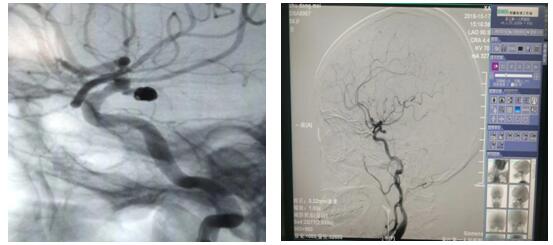

介入栓塞术是通过股动脉穿刺,将纤细的微导管放置于动脉瘤囊内或瘤颈部位,再经过微导管将柔软的钛合金弹簧圈送入动脉瘤囊内或瘤颈部位并将其填充,使得动脉瘤囊内血流消失,促进瘤内血栓形成,治愈动脉瘤。

近日,56岁的朱女士因“左侧面部麻木2天”入院,完善颅脑磁共振及头颈部CTA检查,示左侧颈内动脉与大脑中动脉交界处动脉瘤。DSA检查后,明确诊断“动脉瘤、动静脉畸形”瘤体大小为4-5mm,患者存在病灶侧动眼神经麻痹,考虑瘤体压迫所致,经苏大附二院肖国栋主任会诊后在全麻下行DSA脑动脉瘤栓塞术,整个手术过程顺利,全程用时1.5小时,患者麻醉苏醒后安返病房,经护理人员精心护理,目前患者病情平稳,在积极康复中。颅内动脉瘤介入栓塞术在加勒比扑克玩法详解 是首次开展,手术的成功完成标志着加勒比扑克玩法详解 神经内科脑血管介入治疗又登上了一个新台阶。同时,也填补了加勒比扑克玩法详解 在这一领域的空白。